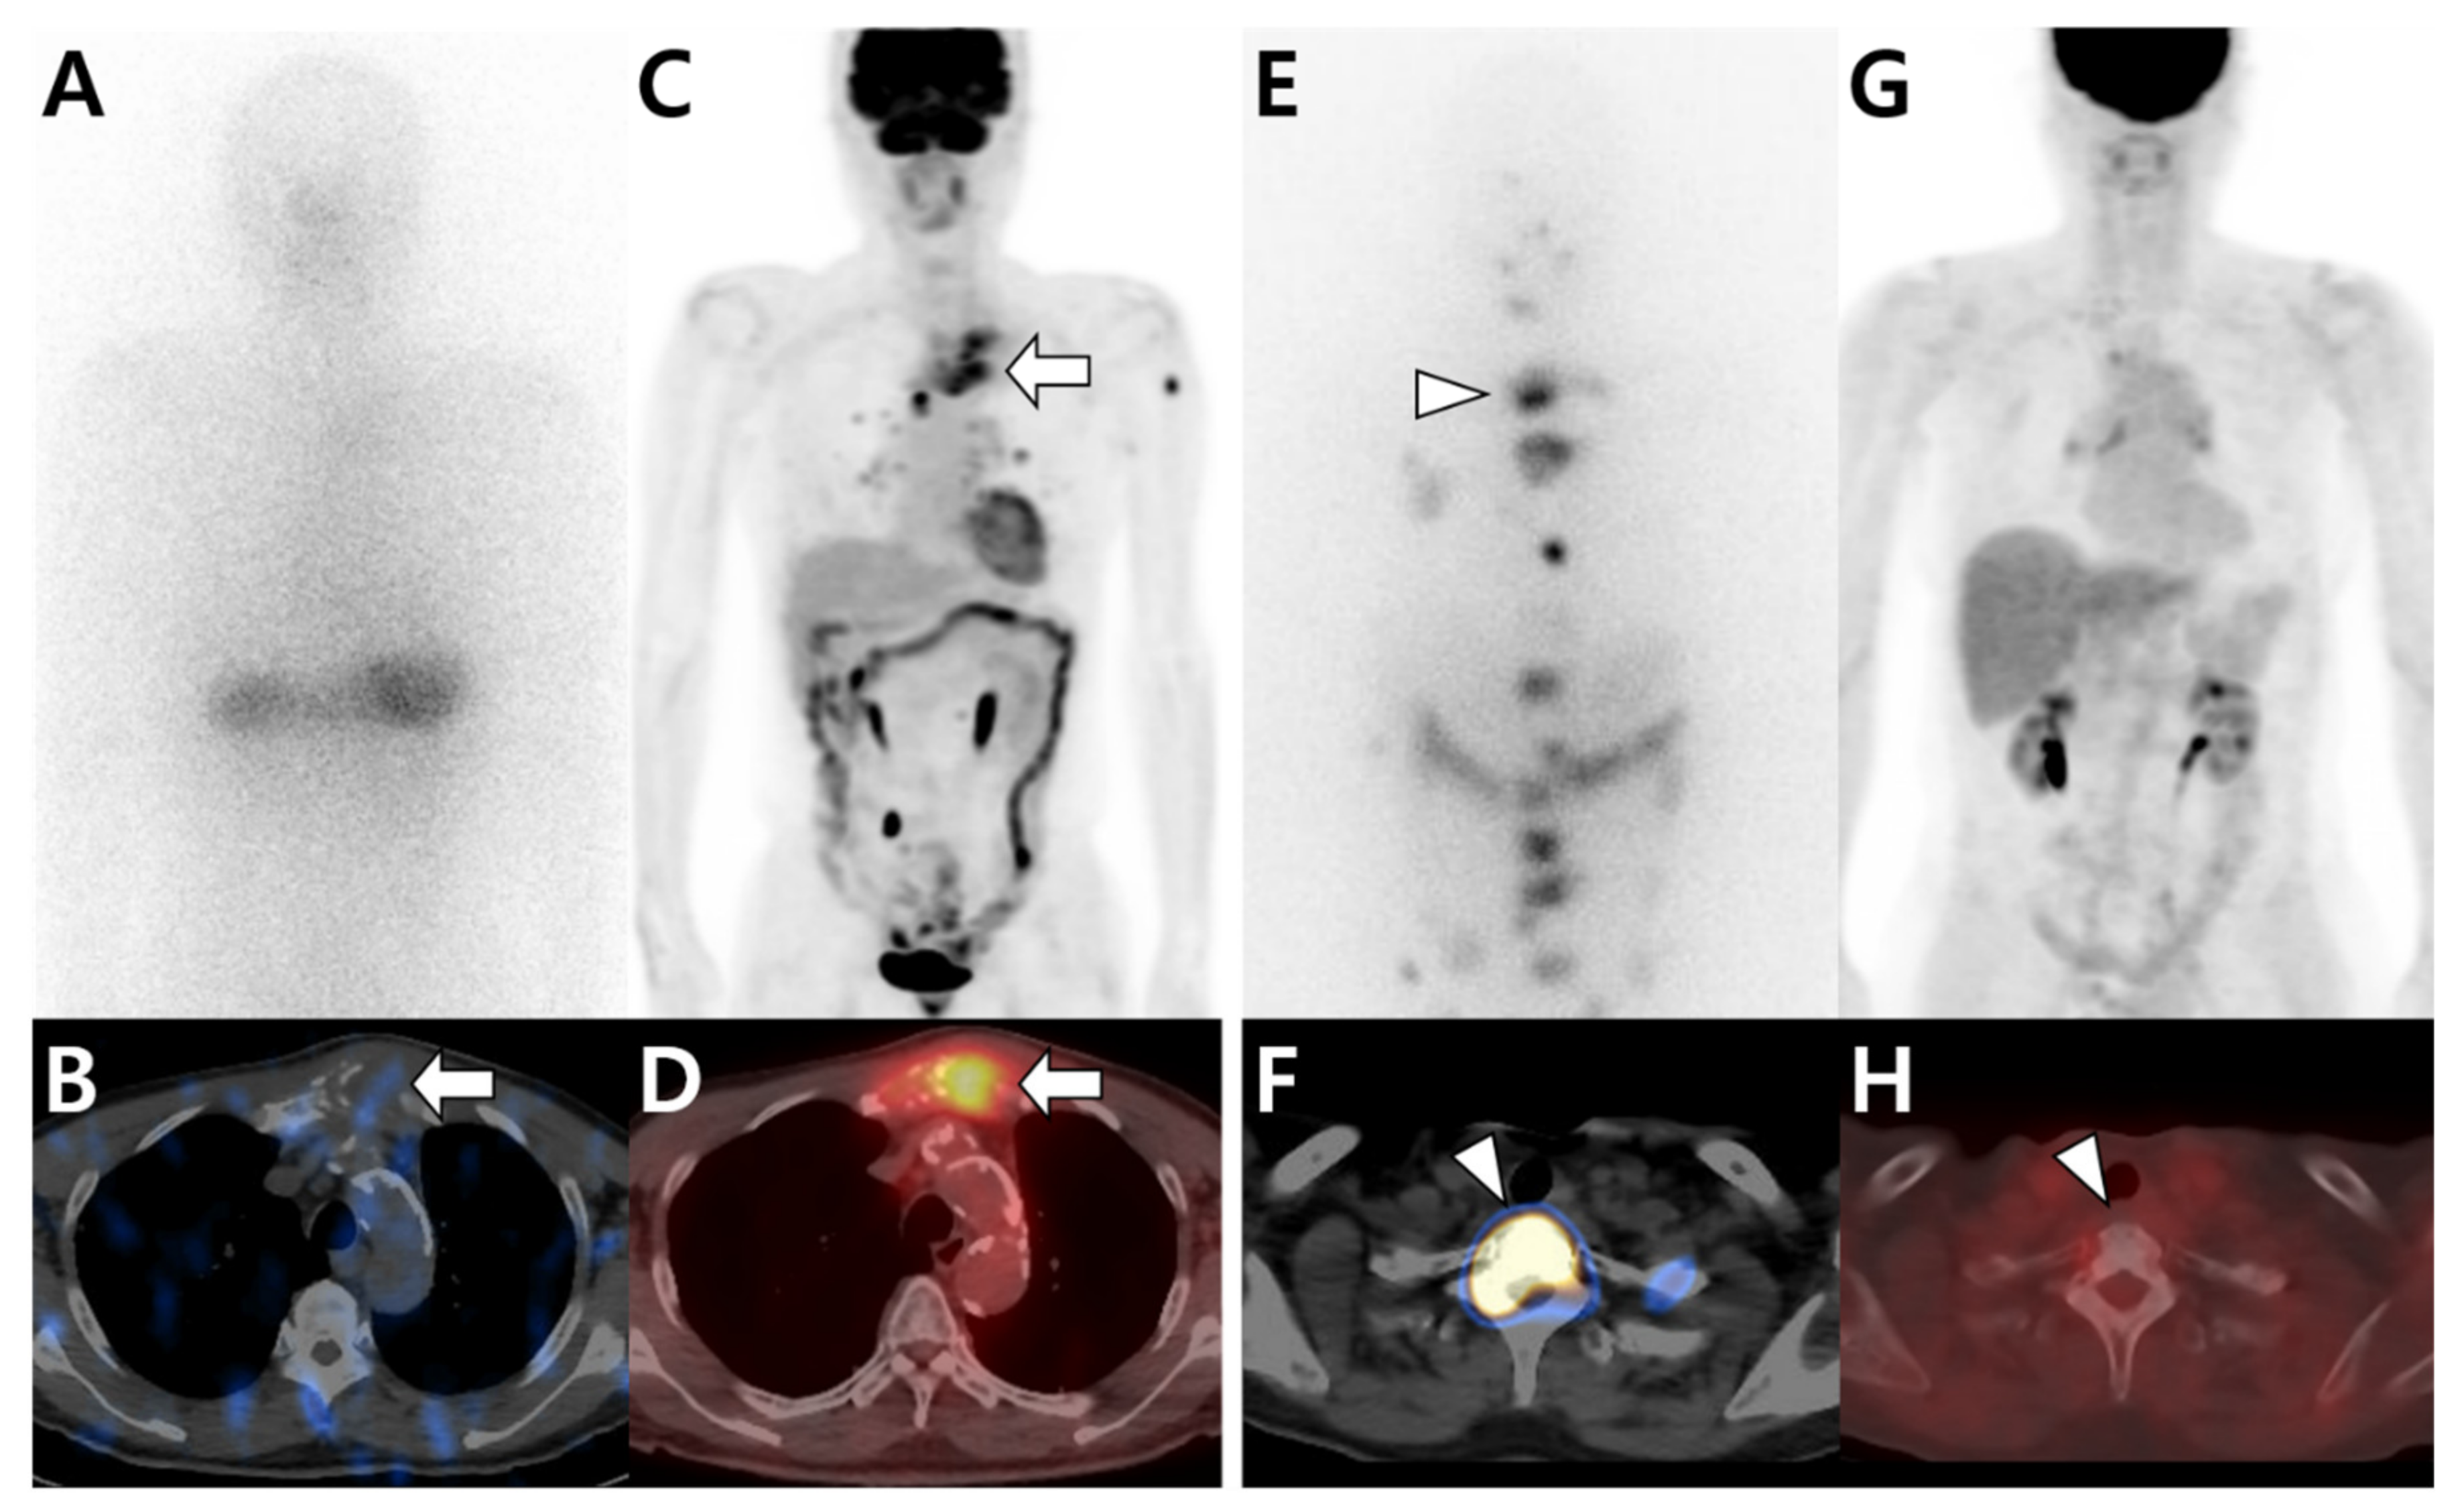

Figure 3.

Different tracer avidities in bone metastases from papillary thyroid carcinoma (PTC) according to differentiation status. (A–D) A 79-year-old male patient with PTC. 131I whole-body scan (A) and single-photon emission computed tomography (SPECT)/computed tomography (CT) (B) show little iodine uptake in metastatic lesions located in the sternum (arrow). In contrast, 18F-fluorodeoxyglucose (18F-FDG) positron emission tomography (PET)/CT (C,D) shows intense FDG uptake in the sternum (arrow). (E–H) A 66-year-old female patient with PTC. 131I whole-body scan (E) and SPECT/CT (F) show multiple iodine uptake in metastatic bone lesions, including those in the T1 vertebra (arrowhead). However, 18F-FDG PET/CT (G,H) shows no significant uptake at the same site.